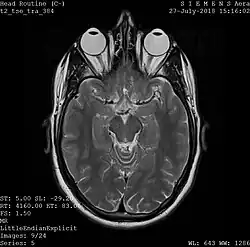

Magnetic resonance imaging

A magnetic resonance imaging instrument (MRI scanner), or "nuclear magnetic resonance (NMR) imaging" scanner as it was originally known, uses powerful magnets to polarize and excite hydrogen nuclei (i.e., single protons) of water molecules in human tissue, producing a detectable signal that is spatially encoded, resulting in images of the body. [11] The MRI machine emits a radio frequency (RF) pulse at the resonant frequency of the hydrogen atoms on water molecules. Radio frequency antennas ("RF coils") send the pulse to the area of the body to be examined. The RF pulse is absorbed by protons, causing their direction with respect to the primary magnetic field to change. When the RF pulse is turned off, the protons "relax" back to alignment with the primary magnet and emit radio waves in the process. This radio-frequency emission from the hydrogen atoms on water is what is detected and reconstructed into an image. The resonant frequency of a spinning magnetic dipole (of which protons are one example) is called the Larmor frequency and is determined by the strength of the main magnetic field and the chemical environment of the nuclei of interest. MRI uses three electromagnetic fields: a very strong (typically 1.5 to 3 teslas) static magnetic field to polarize the hydrogen nuclei, called the primary field; gradient fields that can be modified to vary in space and time (on the order of 1 kHz) for spatial encoding, often simply called gradients; and a spatially homogeneous radio-frequency (RF) field for manipulation of the hydrogen nuclei to produce measurable signals, collected through an RF antenna.

Like CT, MRI traditionally creates a two-dimensional image of a thin "slice" of the body and is therefore considered a tomographic imaging technique. Modern MRI instruments are capable of producing images in the form of 3D blocks, which may be considered a generalization of the single-slice, tomographic concept. Unlike CT, MRI does not involve the use of ionizing radiation and is therefore not associated with the same health hazards. For example, because MRI has only been in use since the early 1980s, there are no known long-term effects of exposure to strong static fields (this is the subject of some debate; see 'Safety' in [[MRI), and therefore there is no limit to the number of scans to which an individual can be subjected, in contrast with X-ray and CT. However, there are well-identified health risks associated with tissue heating from exposure to the RF field and the presence of implanted devices in the body, such as pacemakers. These risks are strictly controlled as part of the design of the instrument and the scanning protocols used.

Because CT and MRI are sensitive to different tissue properties, the appearances of the images obtained with the two techniques differ markedly. In CT, X-rays must be blocked by some form of dense tissue to create an image, so the image quality when looking at soft tissues will be poor. In MRI, while any nucleus with a net nuclear spin can be used, the proton of the hydrogen atom remains the most widely used, especially in the clinical setting, because it is so ubiquitous and returns a large signal. This nucleus, present in water molecules, allows the excellent soft-tissue contrast achievable with MRI. [12]